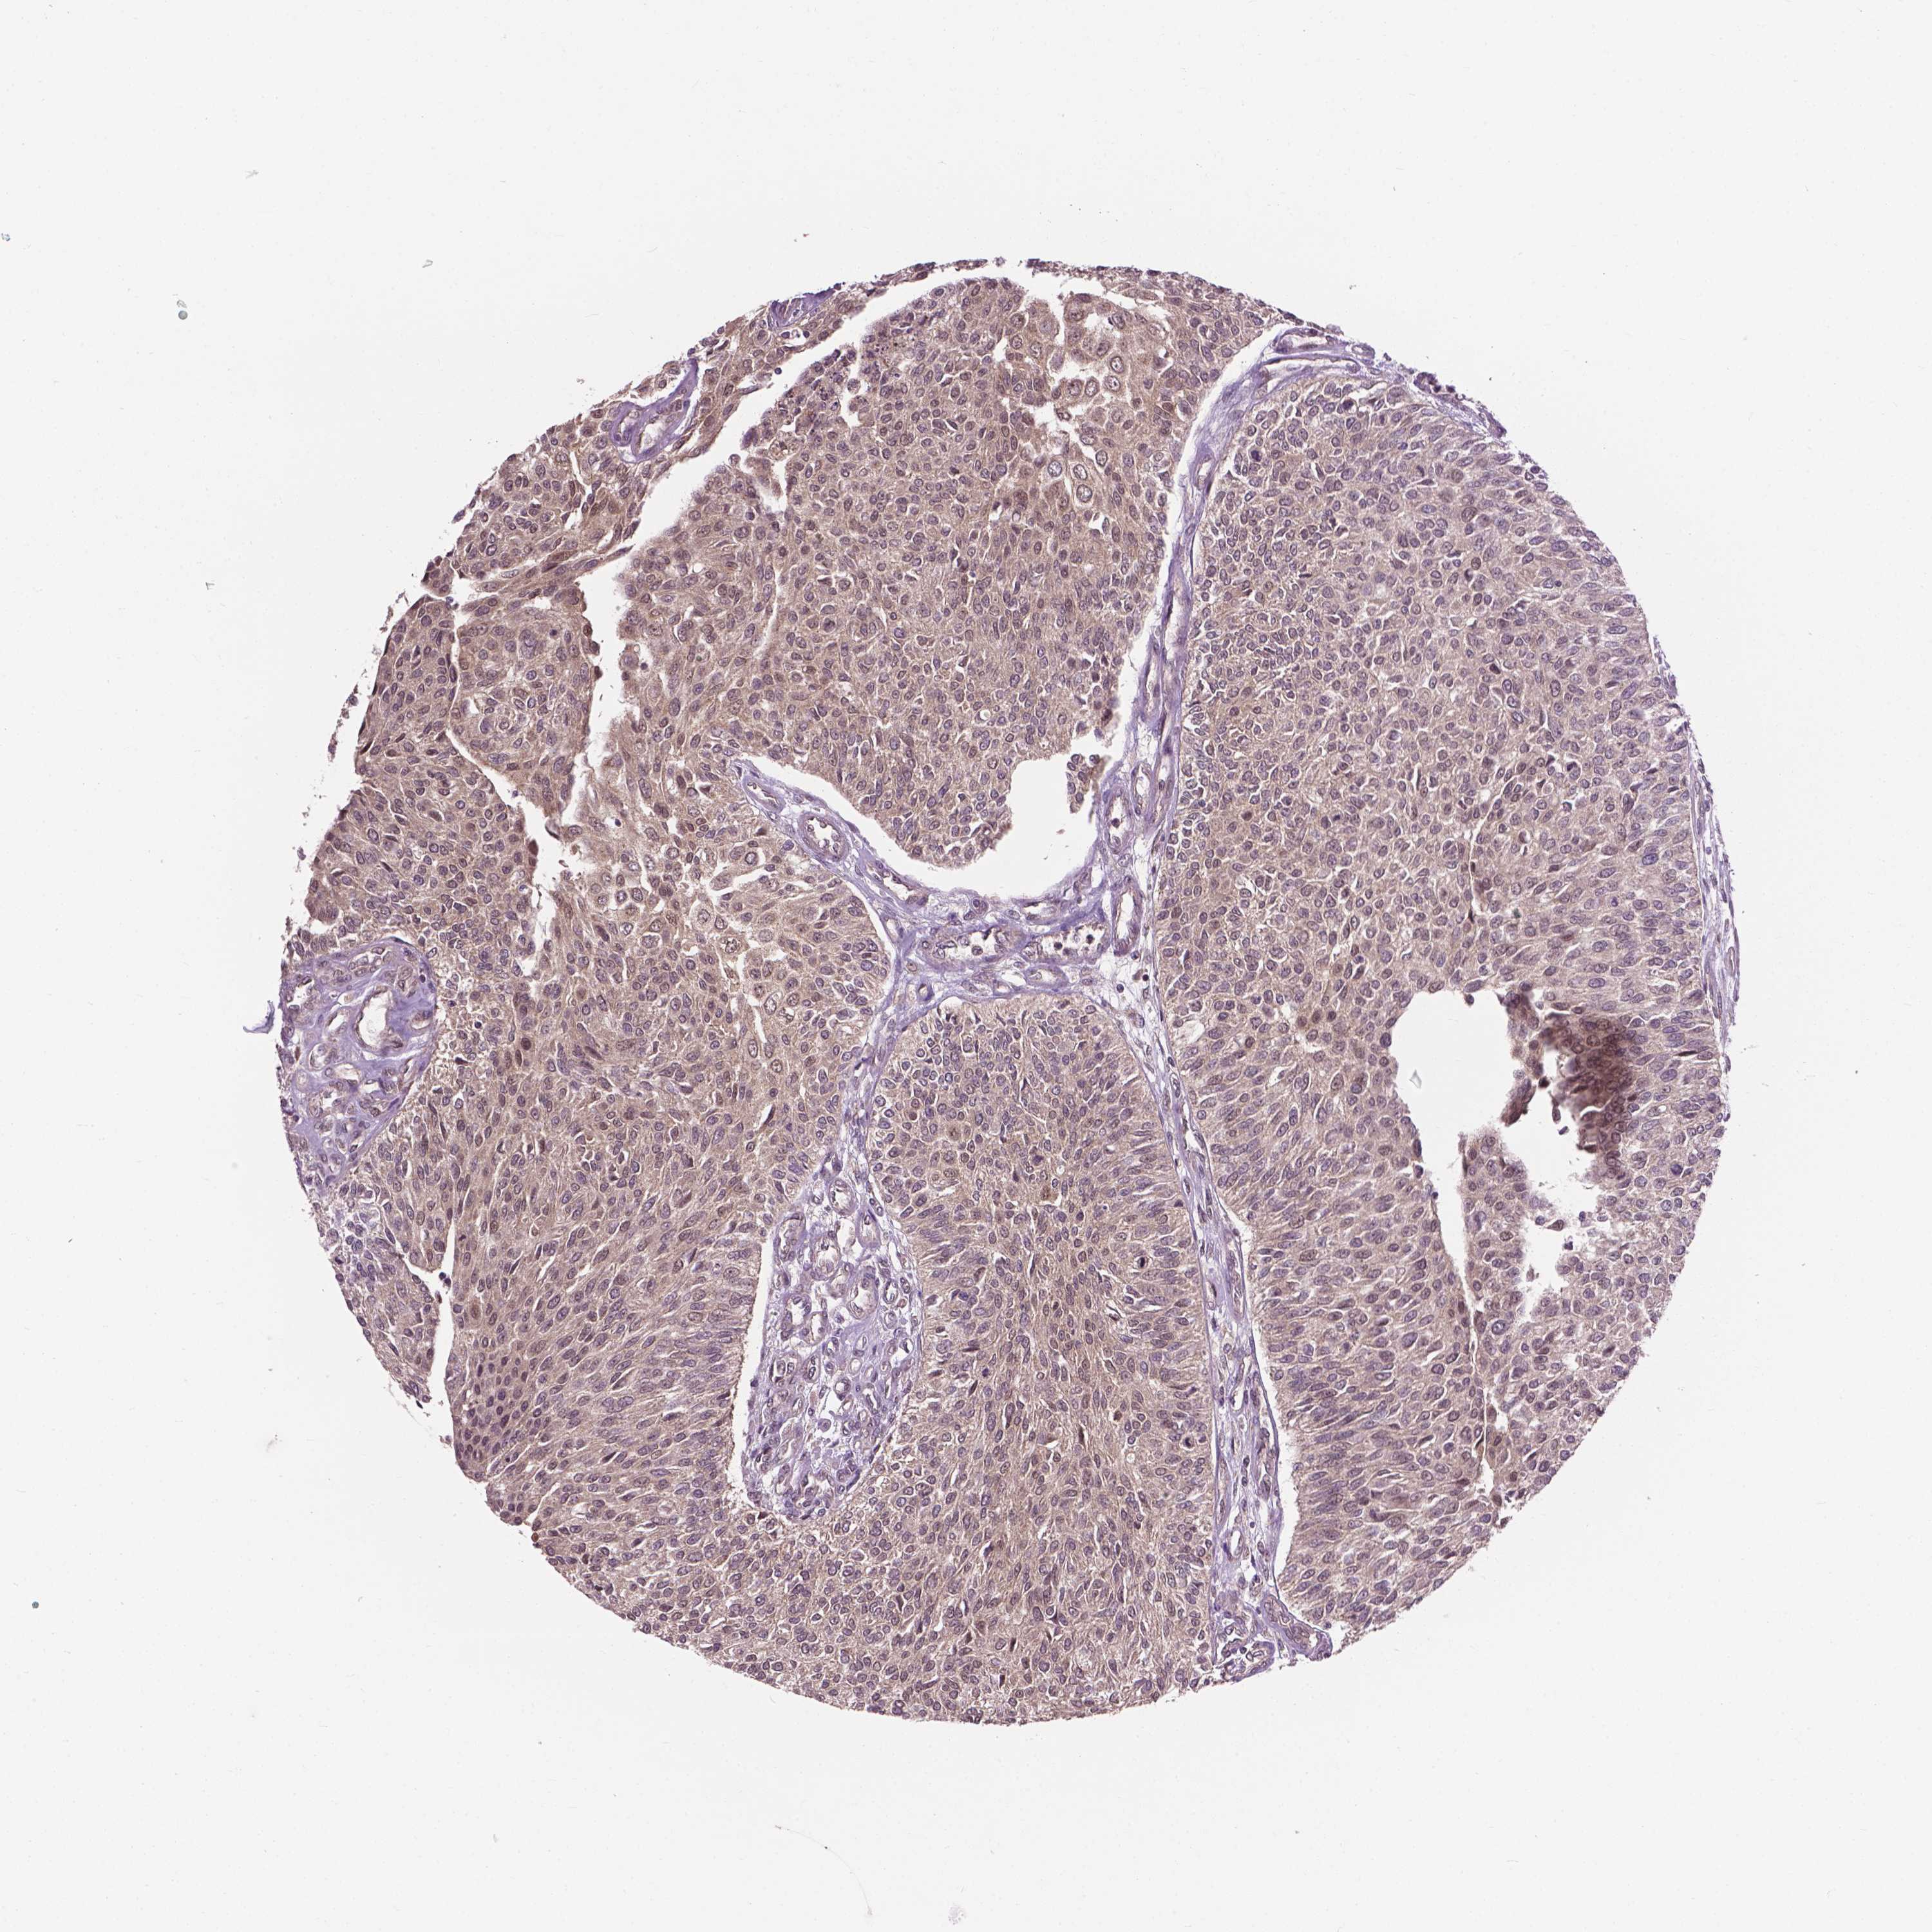

UROTHELIAL CANCER - Protein expressioni

A mouse-over function shows sample information and annotation data. Click on an image to view it in a full screen mode. Samples can be filtered based on level of antibody staining by selecting one or several of the following categories: high, medium, low and not detected. The assay and annotation is described here.

Note that samples used for immunohistochemistry by the Human Protein Atlas do not correspond to samples in the TCGA dataset.

Antibody stainingi

Antibody staining in the annotated cell types in the current human tissue is reported as not detected, low, medium, or high, based on conventional immunohistochemistry profiling in selected tissues. This score is based on the combination of the staining intensity and fraction of stained cells.

Each image is clickable and will lead to virtual microscopy that enables deeper exploration of all samples and also displays staining intensity scores, fraction scores and subcellular localization as well as patient and tissue information for each sample.

Antibody HPA065425

Antibody CAB069426

Urothelial carcinoma, High grade

Urothelial carcinoma, NOS

Urothelial carcinoma, Low grade